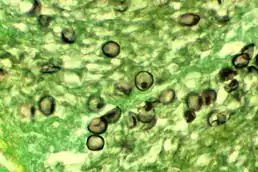

![]() Цисти P. jirovecii у тканині | ||||||||||||||

Таксономічне положення P. jirovecii тривалий час залишалося предметом суперечок, однак в результаті досліджень вчені дійшли висновку, що мікроорганізм належить до царства Грибів. Вивчення мітохондріальних білків, основних ферментів (тиміділатсинтази й дигідрофолатредуктази) та нуклеотидної послідовності рРНК показало, що P. jirovecii ближчий до грибів, ніж до найпростіших. Вивчення біології P. jirovecii ускладнюється тим, що мікроорганізм не росте в культурі. У своєму розвитку він проходить декілька стадій, утворюючи дрібні поліморфні трофозоїти (1—4 мкм), предцисти та цисти (5—8nbsp;мкм). Цисти оточені товстою клітинною стінкою, мають сферичну форму та до 8 спорозоїтів. Трофозоїти є амебоїдними за зовнішнім виглядом та мають одну або більше прозорих сферичних вакуоль та одне ядро в цитоплазмі. Внутрішньоцистні тіла поліморфні, амебоїдні або подовжені. Деякі зрілі цисти мають внутрішньоцистні органи та велику кількість трофозоїтів всередині сотоподібного матеріалу в альвеолярному просторі.[5][6]